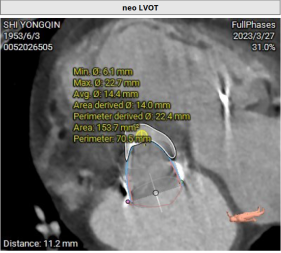

CT评估:既往植入佰仁生物瓣,25#,True ID 23mm, 高度17mm,房间隔穿刺高度约为25.6mm, 模拟植入23mm SAPIEN 3后,Neo-LVOT 153.7mm2 小于170 mm2,aorta-mitral 平面角度125.9°,mitral-septum distance 3mm,有流出道狭窄风险。CT推荐角度为RAO 40°,房间隔无明显钙化、膨出,房间隔长度可满足穿刺需要。拟植入SAPIEN 3 23mmPLUS3ml。